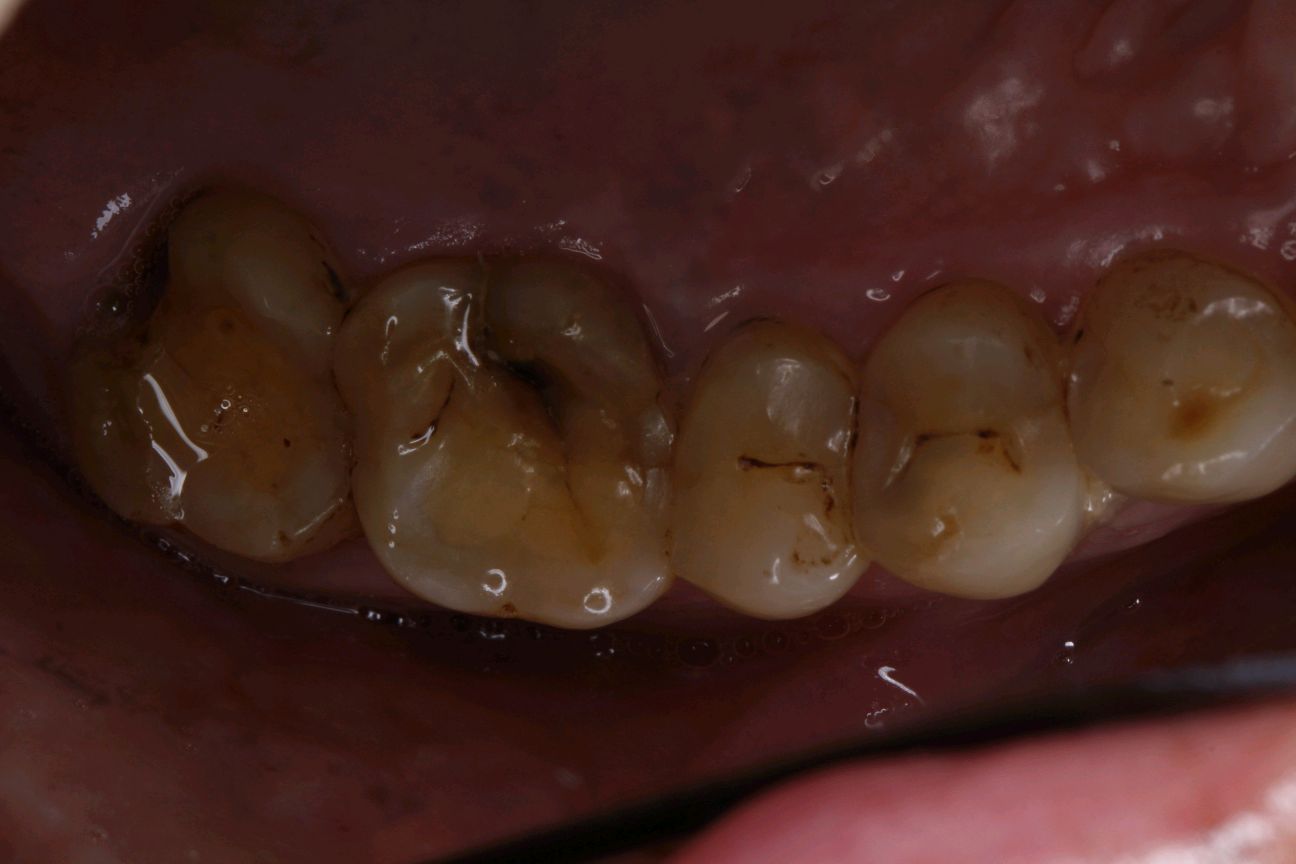

患者男,58岁。多年来感觉后牙咬合刺激痛,吃东西时咀嚼咬不烂,有时牙齿冷热刺激敏感,影响咀嚼,现来我院就诊。

术前照片